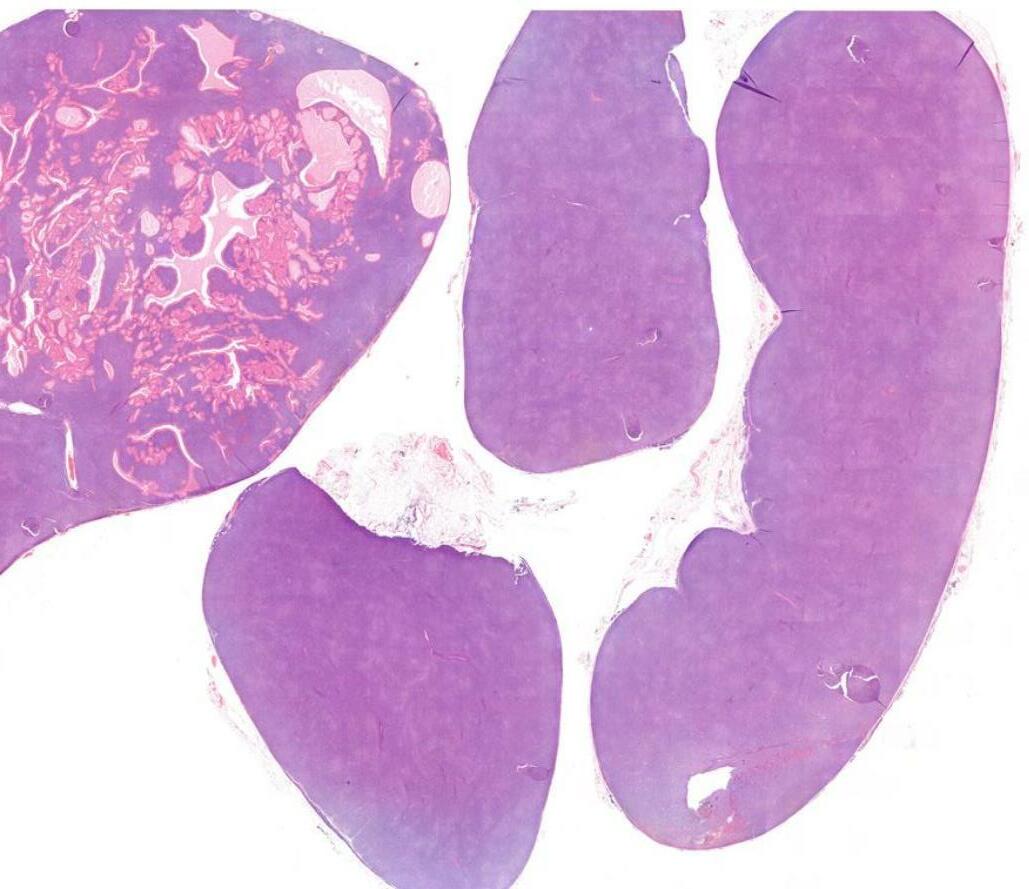

26-year-old, Female, Parotid tumour

Case 1- Salient points • Circumscribed salivary tumour, infiltrative periphery • Papillary cystic, microcystic patterns, hobnailing • Solid sheets of large polygonal cells with granular eosinophilic cytoplasm and vesicular nuclei • Secretory material –colloid-like eosinophilic secretions • Occasional mitotic figures • Work up? PAS, DPAS, • CK7, S100, DOG1, Mammoglobin

Case 1 Diagnosis

Secretory carcinoma

Discussion Differential diagnoses • Acinic cell carcinoma • Secretory carcinoma (previously called MASC) • MEC • 90% -ETV6::NTRK3 fusion -chromosomal rearrangement, t(12;15) (p13;q25) • ETV6::RET, ETV6::MET, ETV6::MAML3 • ETV6 translocation-negative secretory carcinoma. • Similar to Acinic cell carcinoma • But S100+, Mammoglobin+, DOG1-

5th ed Essential and desirable diagnostic criteria • Essential: single cell type with vacuolated colloid-like secretory material; no zymogen cytoplasmic granules; IHC positivity for S100 protein, SOX10, and mammaglobin; lack of IHC staining for p40 and/or p63 • Desirable: ETV6 or RET rearrangement demonstrated by FISH, RNA sequencing, or PCR • Low grade • Lymph node metastases are reported in as many as 25% of cases